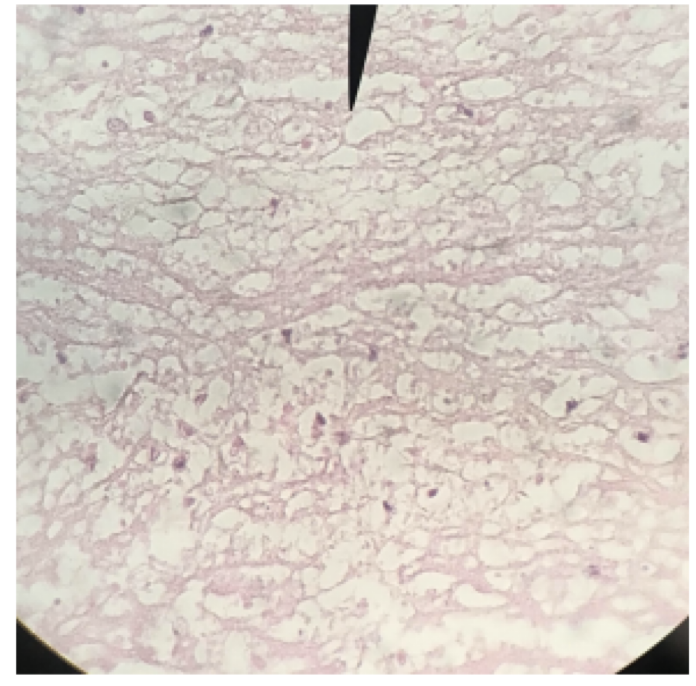

Heart Walls

knowt flashcard image